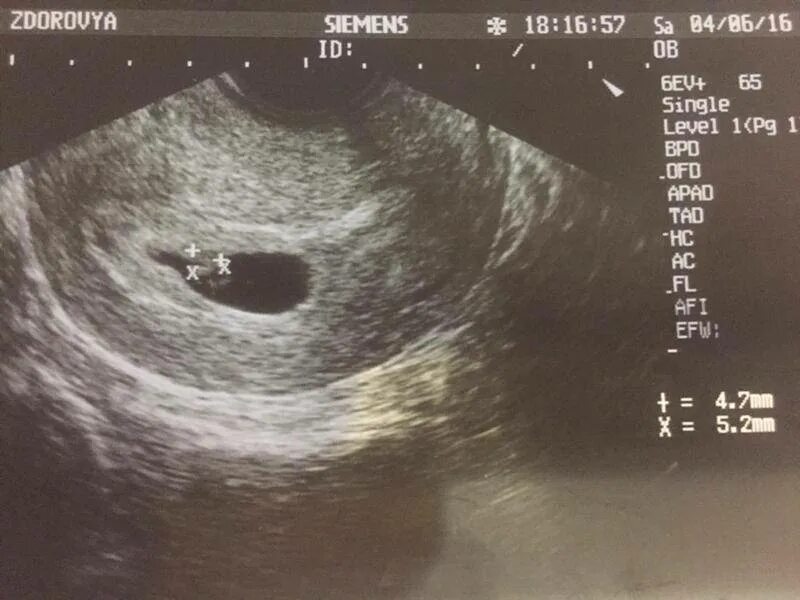

На узи можно определить раннюю беременность